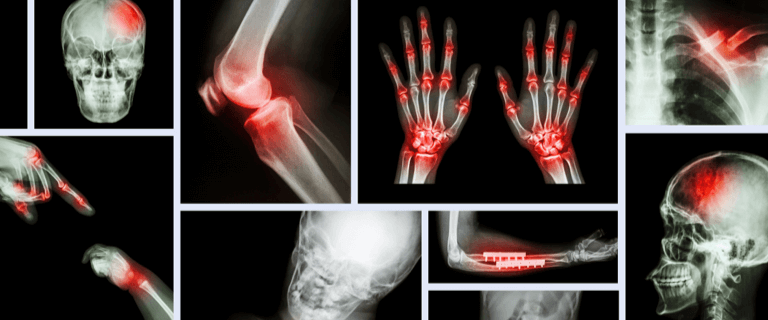

医療用画像で示される全体的な状況に応じて、病症レベル、病巣領域、病巣名などをアノテーションします。

医療用画像で示される全体的な状況に応じて、病巣領域に対してピクセルレベルのセグメンテーションとアノテーションを行ないます。

お客様は脳CTスキャン結果のデータ認識技術の向上を求めていました。アノテーション作業者には医学を学んだバックグラウンドが求められ、画像のハイライトされた領域が出血点であるかどうかを判断し、アノテーションする必要がありました。アノテーションの際、境界の精度が3~5ピクセルを超えないようにし、かつレイヤー(シート)ごとにアノテーションを行ってデータのアノテーション漏れが起こらないようにする必要がありました。Datatangはデータ10000セットのアノテーションを完成させ、お客様による受入検査をクリアしました。